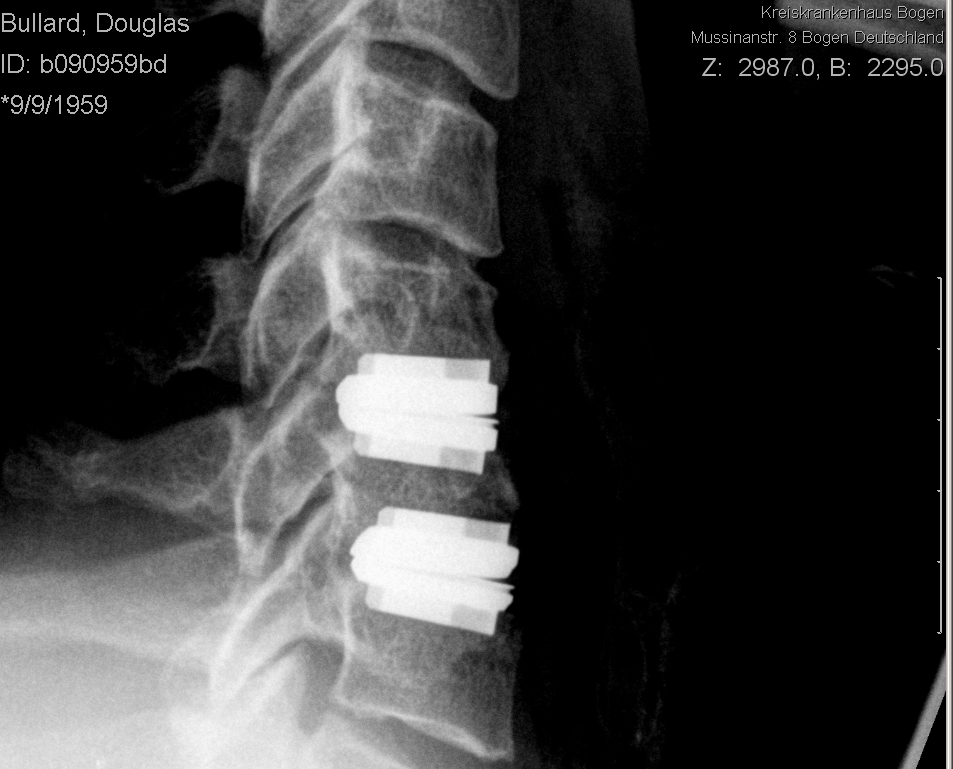

Post op side.jpg preview

The end result - artifical discs. The old discs have been removed, the offending bits of bone removed, and the new joints inserted.